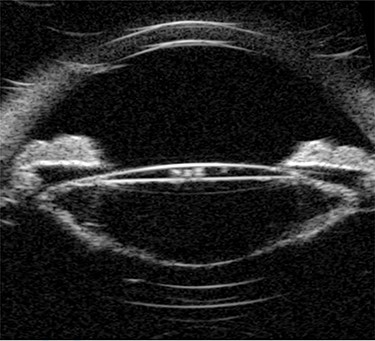

Ultrasound biomicroscopy (UBM) showed dense turbid fluid behind the IOL with varied echogenicity, a severely distended capsular bag, and a thick irregular posterior capsule (Fig. 2). Based on the previous findings, a diagnosis of late onset CBDS was made.

Pre-operative UBM shows a markedly distended capsular bag and thickened posterior capsule.